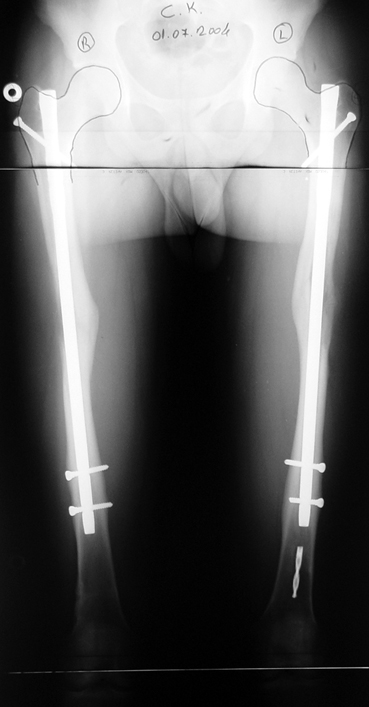

İntramedüller çivinin yerleştirilmesi ve osteotomi: Hasta traksiyon masasına supin pozisyonda yatırılır ve sağlam bacak altta olacak şekilde bacaklar makas pozisyonuna alınır. Standart yolla piriformis çukurundan medulla içine girilir ve kılavuz tel üzerinden kullanılacak çividen 1.5 mm daha kalın oyucu ile medulla oyulur. Proksimal femur, çivinin proksimali daha kalın olduğu için daha kalın oyulur. Radyografide osteotomi hattı planlaması yapılır. Planlama yapılırken uzatma sonunda distalde en az 8 cm. çivi kalması stabilizasyon için gereklidir. Kortikotomi perkütan olarak kortikotom ile tamamlanır. Daha sonra kılavuz tel çivinin boyunu ölçmek için distale ilerletilir. Uygun boyda intramedüller çivi çakılır. Son olarak çivi proksimalden kilitlenir ve bir adet dren konarak ameliyatın birinci kısmı tamamlanır.

Eksternal fiksatör uygulanımı: İntramedüller çiviye değmeden aşağıya ve yukarıya üçer adet Schanz vidası gönderilir. Vidalarla çivi arasında en az 1 mm den fazla mesafe olmalıdır.

Biz son zamanlarda, seçilmiş vakalarda, uzatma sonrası uzunluğu ve “alignment’ı” korumak amacı ile unilateral dinamik aksiyel fiksatör ve kilitli intramedüller çivi kombinasyonunu tercih etmekteyiz. Bu yöntemin ön şartları medullanın en dar çapının 7 mm.’den geniş olması ve uzatma sonrası distalde en az 8 cm. uzunluğunda çivi kalabilmesidir. İntramedüller çivi hem uzatma esnasında femurun üzerine gelen makaslama ve bükülme kuvvetlerini nötralize etmekte hem eksternal fiksasyon süresini kısaltmakta, hem de yeni oluşan kemiği kırıklara karşı korumaktadır. Serimizde bir vakada subtrokanterik femoral osteotomi yapılmıştır. İntramedüller çiviye rağmen varus angulasyonu oluşması yönünde bir dezavantaj tespit etmedik.